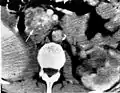

Pancreatic serous cystadenoma

Pancreatic serous cystadenoma is a benign tumour of the pancreas.[2] It is usually solitary and found in the body or tail of the pancreas, and may be associated with von Hippel–Lindau syndrome.[2]